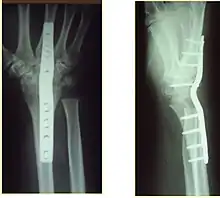

Surgery

Surgery is generally indicated for displaced or unstable fractures.[18] The techniques of surgical management include open reduction internal fixation (ORIF), external fixation, percutaneous pinning, or some combination of the above. The choice of operative treatment is often determined by the type of fracture, which can be categorized broadly into three groups: partial articular fractures, displaced articular fractures, and metaphyseal unstable extra- or minimal articular fractures.[5]

If the fractures are unlikely to be reduced by closed means, open reduction with internal plate fixation is preferred.[5] Although major complications (i.e. tendon injury, fracture collapse, or malunion) result in higher reoperation rates (36.5%) compared to external fixation (6%), ORIF is preferred, as this provides better stability and restoration of the volar tilt.[5][23] Following the operation, a removable splint is placed for 2 weeks, during which time patients should mobilize the wrist as tolerated.[5]